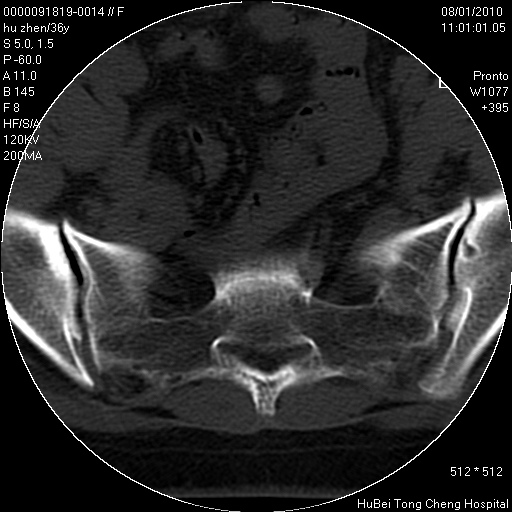

患者 女,36岁。右侧腰腿痛半月余。腰骶椎mr平扫偶然发现骶椎异常信号。

临床诊断:1)腰椎间盘突出症。2)骶椎肿瘤性病变?

骶椎ct平扫(层厚、层距均为5mm),图像如下: